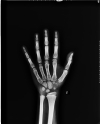

Ergenlik bulgularının kız çocuklarında 8 yaş, erkek çocuklarında ise 9 yaşından önce ortaya çıkmasına “Erken Ergenlik” denir. Bu durum genellikle ergenlik hormonlarının zamanından önce faaliyete geçmesi sonucu ortaya çıkar. Olguların bir kısmında buna neden olabilecek altta yatan ciddi bir problem var iken bir kısmında yalnızca hipofizer zamanlama hatası olabilmektedir. Nedeni ne olursa olsun Erken Ergenlik çocuğun hem ruhsal hem de fiziksel gelişimini etkileyen bir durumdur. Bazen de ergenliğin başlama yaşı normal olup ilerlemesi çok hızlı olabilmektedir. Her iki durumda da kemik yaşı hızlı ilerleyerek büyümenin erken durmasına ve ve boy kısalığına yol açar. Bu çocuklar hem altta yatan neden hem de tedavi açısından zaman yitirilmeden değerlendirilmelidirler.